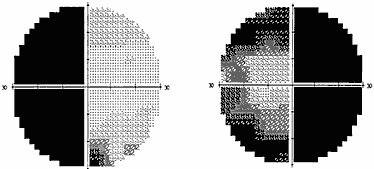

Хиазмальный синдром включает в себя битемпоральные дефекты поля зрения (рис. 1) и побледнение дисков зрительных нервов по типу первичной нисходящей атрофии.

Рис. 1. Полная битемпоральная гемианопсия (автоматическая статическая периметрия)

При наиболее часто встречающемся срединном варианте расположения хиазмы опухоль начинает сдавливать центральные перекрещенные волокна нижней поверхности хиазмы, идущие от носовых половин сетчатки. Клинически это проявляется появлением дефектов в верхних височных квадрантах поля зрения на обоих глазах – начальный хиазмальный синдром.

Следует отметить, что дефекты в поле зрения поначалу можно выявить только с помощью цветных объектов, красного и зеленого. Исследование поля зрения на цвета более чувствительно, чем кинетическая периметрия на белый цвет. Острота зрения на этом этапе развития заболевания, как правило, сохраняется нормальной. Диски зрительных нервов обычной окраски. Постепенно, по мере роста опухоли, усугубляются битемпоральные дефекты поля зрения, начальный хиазмальный синдром переходит в развернутый хиазмальный синдром с полным или почти полным выпадением височных половин поля зрения. Появляется побледнение дисков зрительных нервов преимущественно в височной половине – развивается первичная нисходящая атрофия зрительных нервов. Важно знать, что изменения на глазном дне наступают спустя месяцы от момента развития первых дефектов поля зрения.